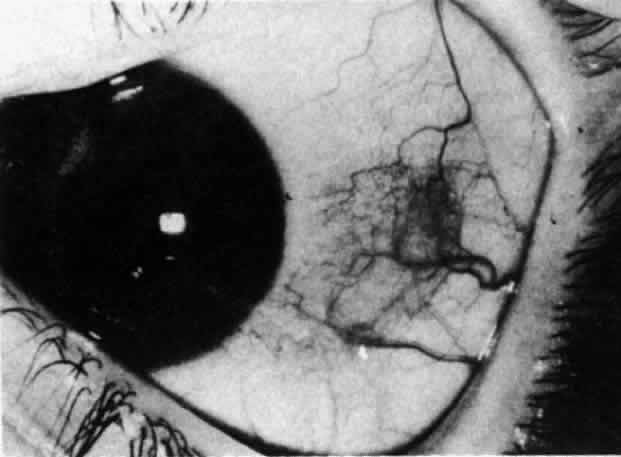

The redness of simple episcleritis may be intense, varying from a fiery-red or a brick-red discoloration to a mild red flush, but it does not have the bluish tinge that is seen in scleritis. The distribution is usually sectorial but can involve the whole anterior segment of the globe. The episcleral vessels are engorged but retain their normal radial position and architecture (Figs. 13 and 14; Color Plate 1A). In simple episcleritis, there is a diffuse edema of the episcleral tissues. These tissues are sometimes infiltrated with gray deposits that appear yellow in red-free light. Surprisingly, the eye is rarely tender to the touch.

Fig. 13. Infiltration of the episclera in which the superficial episcleral vessels show maximal congestion. Conjunctival vessels are slightly congested, as is the deep episcleral plexus, whose irregular criss-cross pattern can be seen deep to the radially arranged superficial episcleral plexus.

Fig. 14. Diffuse inflammation. Superficial vessels are maximally engorged and retain their radial pattern and architecture. (See Figures 27 and 34.) (Watson PG: Connective tissue disorders and the eye. In: Recent Advances in Ophthalmology, Vol 5, pp 214–277. London, Churchill-Livingstone, 1975)